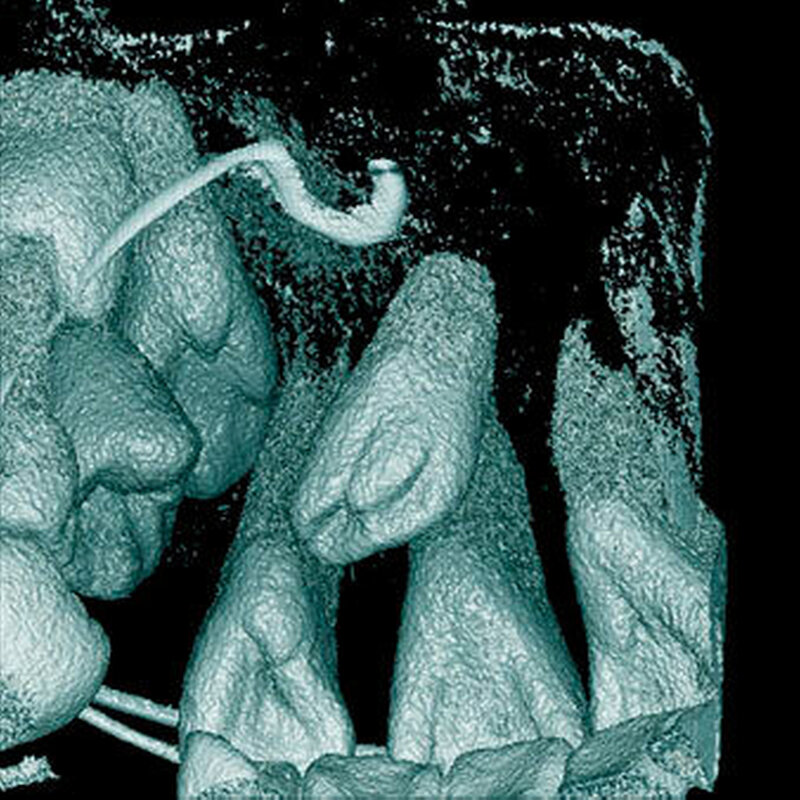

Krümmung, verzögerte oder abnormale Entwicklung der Wurzeln der Nachbarzähne

Eine Verzögerung, Krümmung oder sonstige abnormale Entwicklung benachbarter Zahnwurzeln scheint selten zu sein, und es sind nur wenige Fallberichte bekannt [Yeung et al., 2003; Hansen Kjaer, 2004; Arslan et al., 2008].

Bei überzähligen Zähnen werden vier morphologische Typen unterschieden: konisch (Abbildung 9), tuberkulär (höckerförmig; Abbildung 10), überzählige Zähne mit identischer Zahnform (Abbildung 11) und Odontom (Abbildung 12) [GARVEY et al. 1999]. Der konische überzählige Zahn ist ein kleiner, zapfenförmiger Zahn und zudem der häufigste Fall im bleibenden Gebiss [Rajab Hamdan 2002, Liu et al. 2007, Gündüz et al., 2008; Ferrés-Padró et al., 2009; Hyun et al., 2009; Schmuckli et al., 2010; Mossaz et al., 2014]. Er kommt oft zwischen den oberen zentralen Schneidezähnen vor und entwickelt sich gleichzeitig zur Wurzelbildung der bleibenden Schneidezähne. Konische überzählige Zähne führen meist nicht zu einer Durchbruchstörung oder -behinderung der zentralen Schneidezähne. Tuberkuläre, überzählige Zähne sind größer als der konische Typ und besitzen einen zusätzlichen charakteristischen Höcker oder Tuberkel der Zahnkrone. Sie kommen oft gepaart vor und liegen in der Regel palatinal der oberen mittleren Schneidezähne. Im Gegensatz zu konischen überzähligen Zähnen brechen die meisten tuberkulären nicht in die Mundhöhle durch und es kommt nicht selten zur Durchbruchstörung oder -behinderung der zentralen Schneidezähne [Mason et al., 2000; Minguez-Martinez et al., 2012]. Überzählige Zähne mit identischer Zahnform sind Zähne, welche vom eigentlichen Zahn in der Lage (also in der Zahnreihe gelegen) und Form nicht zu unterscheiden sind.

Überzählige Zähne können sich in der Richtung des normalen Durchbruchs entwickeln oder sie können inkliniert, horizontal oder in einer umgekehrten Position (invers) liegen. Ungefähr ein Drittel bis die Hälfte der überzähligen Zähne in der Oberkieferfront zeigen eine inverse Position [Humerfelt et al., 1985; Koch et al., 1986; von Arx, 1990; Tyrilogou, 2005; Liu et al., 2007; Gündüz et al., 2008; Hyun et al., 2009; Mossaz et al., 2014].